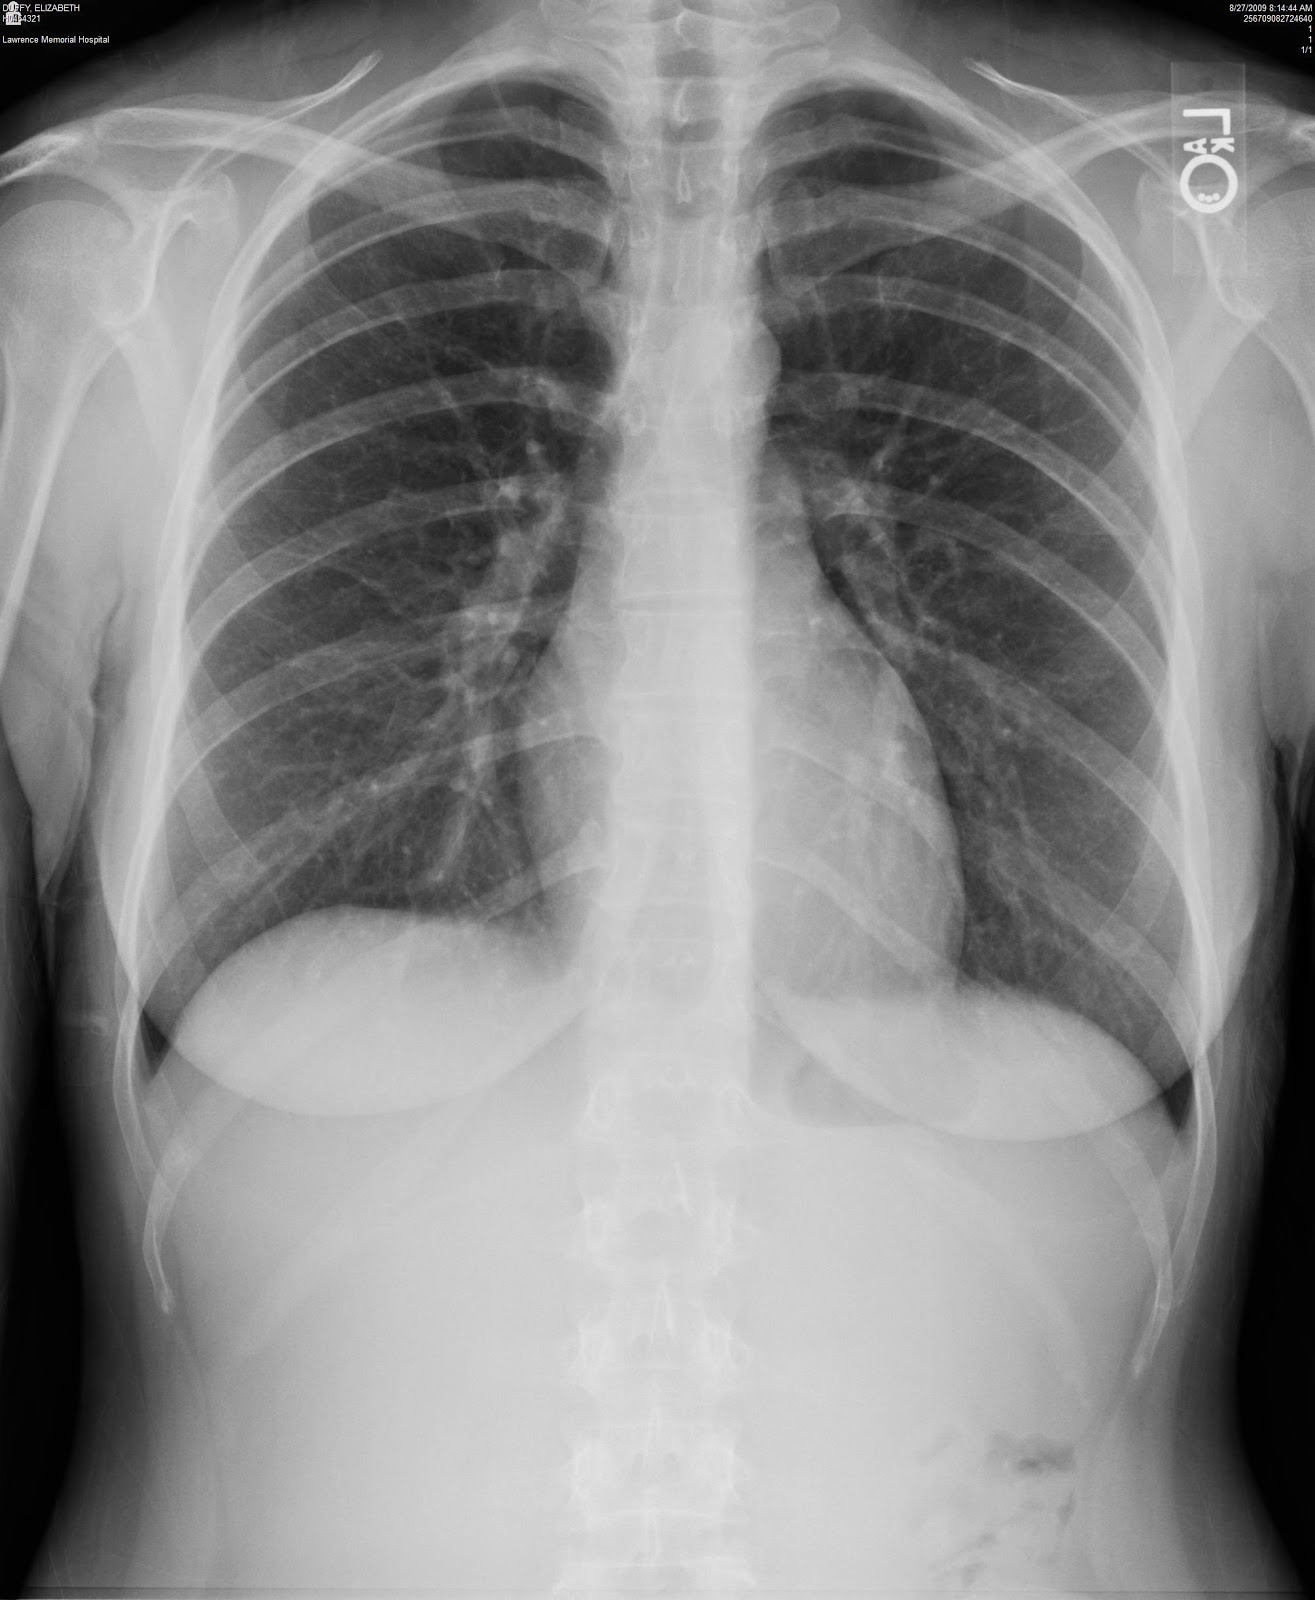

A s keletal survey demonstrates innumerable well circumscribed �punched out� lytic lesions best seen in the lateral view of the skull. Loss or thinning of bone (osteoporosis or osteopenia) holes in bone (lytic lesions), and/or. A study of the international myeloma working group.

Skeletal survey in multiple myeloma: Features are in keeping with multiple myeloma. My myeloma is under control and i haven�t had any bone involvement from the disease.